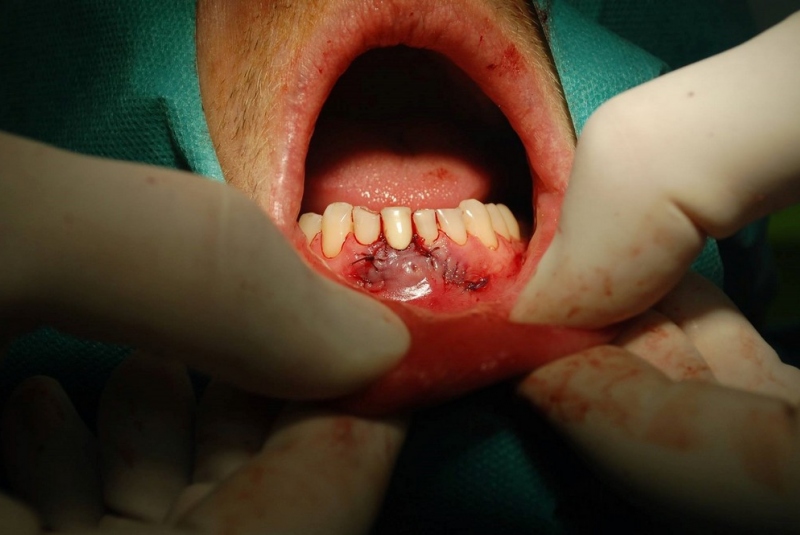

- Resekcia (odstránenie zápalového ložiska zubného pôvodu)

- Excízie (odsránenie patologických ložísk, vrátane histologického vyšetrenia)

- Plastiky (rôzneho rozsahu)